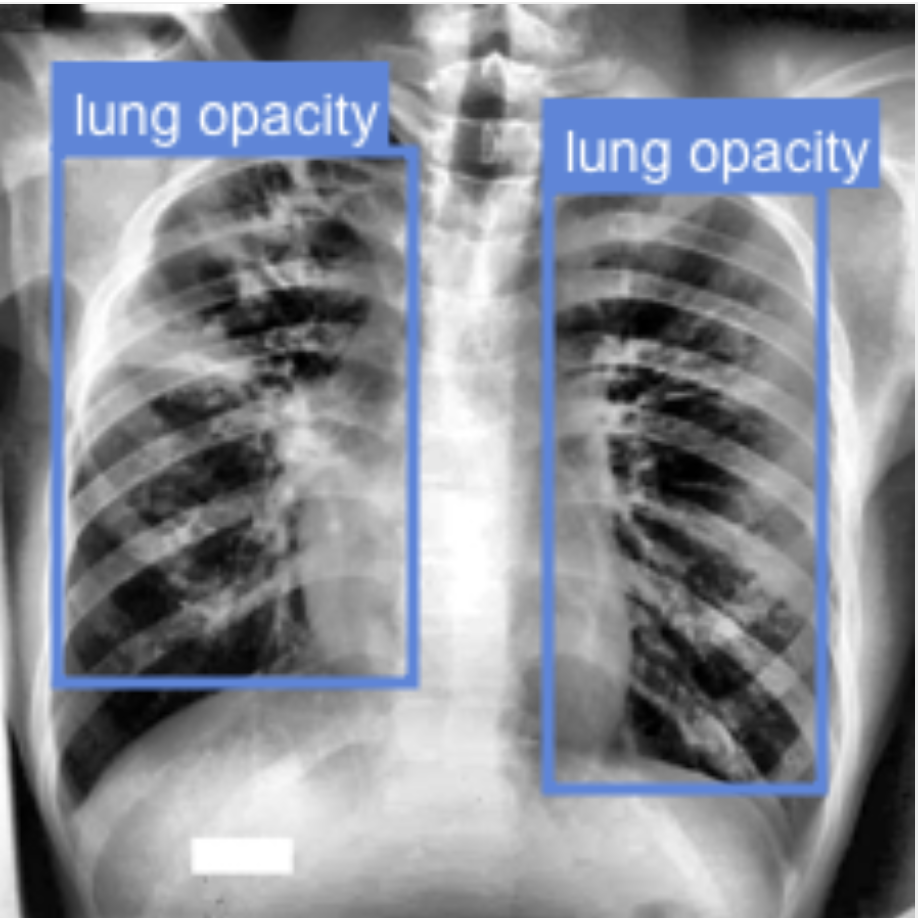

Figure 4 shows the bounding boxes predicted by PaliGemma-CXR. PaliGemma detects the pathologies in the image. It can detect multiple instances of the same pathology as well as different pathologies occurring within the same image.

Refer to caption

(a)

(b)

(c)

(d)

Figure 4: (a) shows the bounding boxes predicted by PaliGemma-CXR and (b) shows the ground truth bounding boxes, (c) shows the ground truth segmentation mask and (d) shows the segmentation mask generated by PaliGemma-CXR.